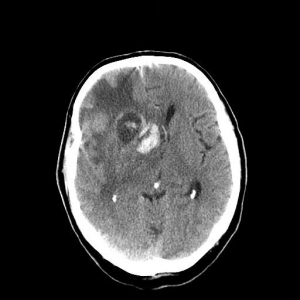

Where is the aneurysm likely to be in this patient?

The location of the haemorrhage can help localise the site of the ruptured aneurysm.

Anterior Comm Artery Aneurysm:

MCA aneurysm: (previous case)

PCA aneurysm (see below)